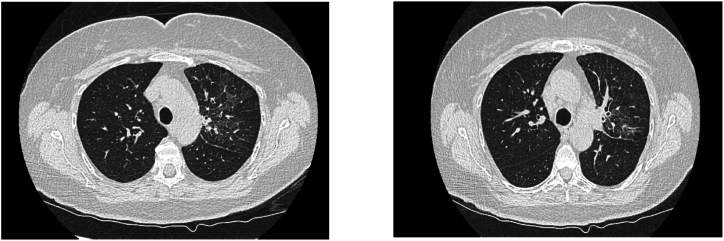

间变性淋巴瘤激酶酪氨酸激酶抑制剂(ALK TKIs)显示出强大的疗效,并彻底改变了ALK重排的非小细胞肺癌患者的治疗。ALK TKIs可产生副作用,有时甚至严重,如肺炎。我们报告一例ALK阳性晚期非小细胞肺癌患者在一线阿勒替尼治疗期间发生肺炎。由于没有确定肺炎的其他病因,患者接受皮质类固醇治疗并停用阿勒替尼。在快速的临床恢复和影像学检查后,患者开始使用布加替尼,没有复发的临床症状或肺炎的影像学表现。虽然需要进一步的描述,但我们的经验表明,对于一些服用ALK- tki后出现药物性肺炎的患者,改用第二种ALK- tki可能是一种安全的治疗选择。

We report a case of a patient with ALK positive advanced NSCLC who developed pneumonitis during treatment with first-line alectinib. With no alternative etiology of pneumonitis identified, the patient was treated with corticosteroids and discontinuation of alectinib. Following rapid clinical recovery and radiographic resolution of the opacities, the patient was started with brigatinib, with no recurrence of the clinical symptoms or radiographic findings of pneumonitis. While further descriptions are needed, our experience suggests that switching to a second ALK-TKI may be a safe therapeutic option in some patients who develop drug-induced pneumonitis on ALK TKIs.